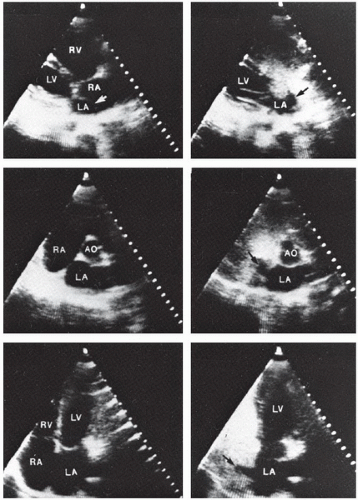

Shunt Detection And Quantification Thoracic Key

Valve Area Calculation Shunt Detection And Quantification Ppt Download